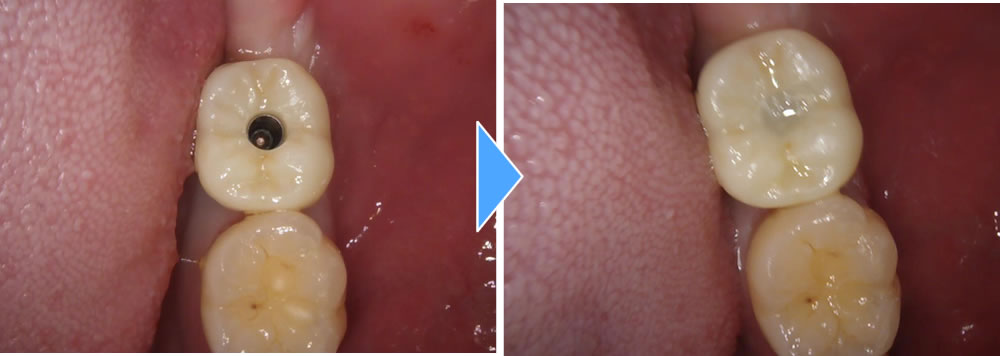

上部構造の装着・治療完了

インプラントと顎骨がしっかりと結合したことを確認した後、製作した上部構造を装着し、咬み合わせを調整して治療完了です。治療後は、もともとあった歯と同じようにしっかりと噛むことができ、大変満足していただいております。